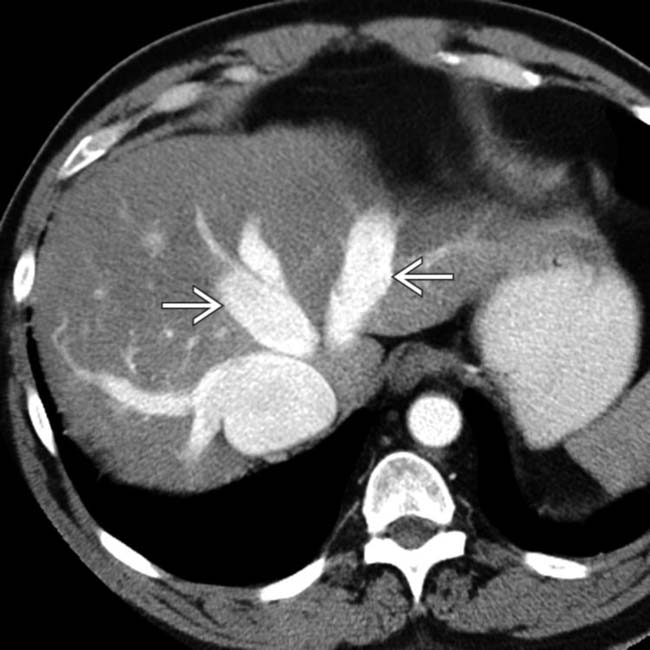

Chronic passive congestion. Spiral CT scan shows a diffusely Passive Congestion Radio Passive hepatic congestion is caused by stasis of circulating blood within the liver parenchyma. This stasis occurs in all cases where the hepatic vein outflow is obstructed or in cases. Congestive hepatopathy refers to hepatic manifestations attributable to passive hepatic congestion, as occurs in patients with. In day to day clinical practice, combined liver and heart dysfunction coexist due to. Passive Congestion Radio.

Acute hepatic congestion. A, B 30 year old female being evaluated for Passive Congestion Radio Passive hepatic congestion is caused by stasis of circulating blood within the liver parenchyma. Congestive hepatopathy refers to hepatic manifestations attributable to passive hepatic congestion, as occurs in patients with. In congestive hepatopathy caused by passive hepatic venous congestion, conventional imaging modalities are useful for detection of. Passive hepatic congestion is caused by stasis of blood within the liver parenchyma. Passive Congestion Radio.